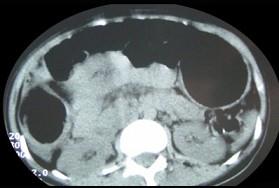

女,30岁,便秘、腹痛腹胀多年,CT检查如图,最可能的诊断是 ( )A.结肠肠梗阻B.先天性巨结肠C.结肠肠套叠D.结肠肠扭转...

问题 女,30岁,便秘、腹痛腹胀多年,CT检查如图,最可能的诊断是 ( )

选项 A.结肠肠梗阻 B.先天性巨结肠 C.结肠肠套叠 D.结肠肠扭转 E.结肠肠栓塞

答案 B